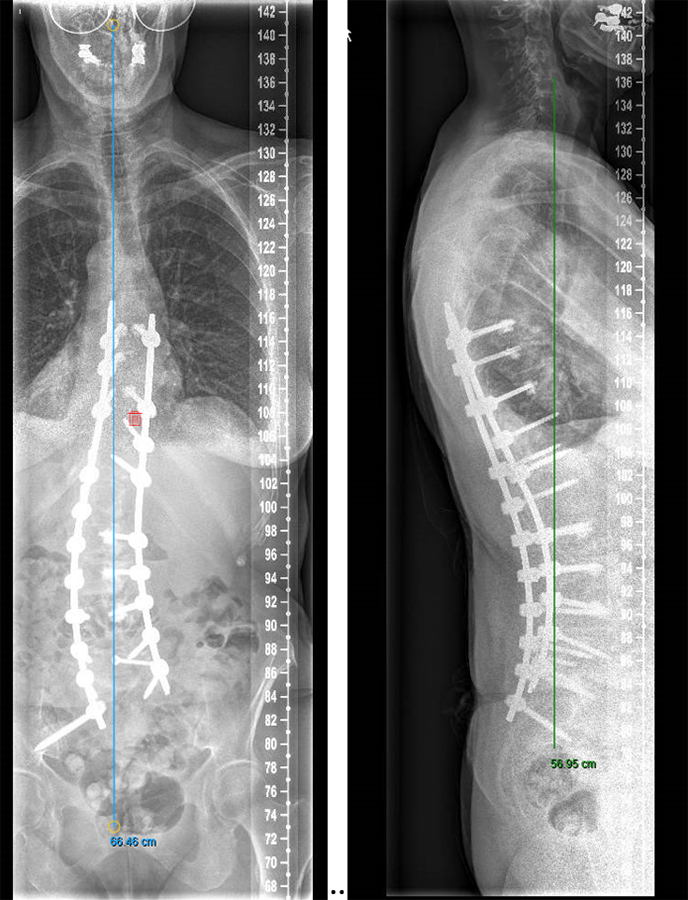

We performed a posterior fusion and correction of Th8-S2-SI-Ilium (Fig 6). In Th9, Th10, Th11, and Th12 we instrumented only unilateral pedicle screws due to small pedicle diameters. A S2-SI-Ilium screw was placed on the left side. A supplemental translaminar screw was used at L5-S1 on the right side. We augmented the screws in Th8, Th9, Th10, L2, L3, and L4. Additionally, a TLIF approach was performed on L2-3 and L3-4 with autogenous bone as interbody support. No complications occurred during nor after surgery, and she remained in good balance during the 1-year postoperative follow-up.